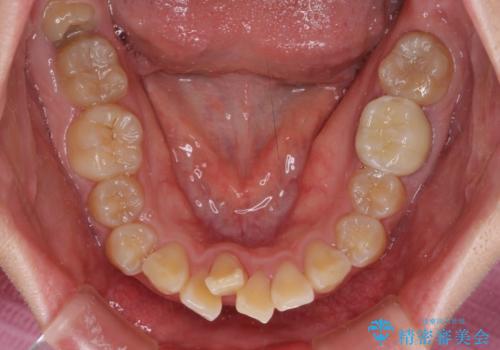

- クリアブラケット

- 2年4ヶ月

- 口元の閉じにくさと、前歯のでこぼこの歯並びを気にして来院された患者様です。

口元を積極的に引っ込めるために、上下左右の小臼歯計4本を抜歯することとしました。

4本の歯を抜歯したことで、飛び出していた口元が引っ込み、横顔が大きく改善されました。